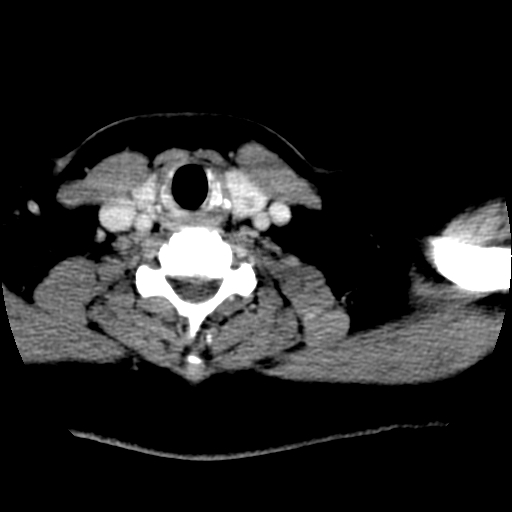

标题: CT25491:女,55岁,发现左侧甲状腺肿块一个月。 [打印本页]

女,55岁,发现左侧甲状腺肿块一个月,彩超示:甲状腺多发结节伴左叶结节液化。

腺瘤囊变

考虑左侧甲状腺腺瘤囊变。